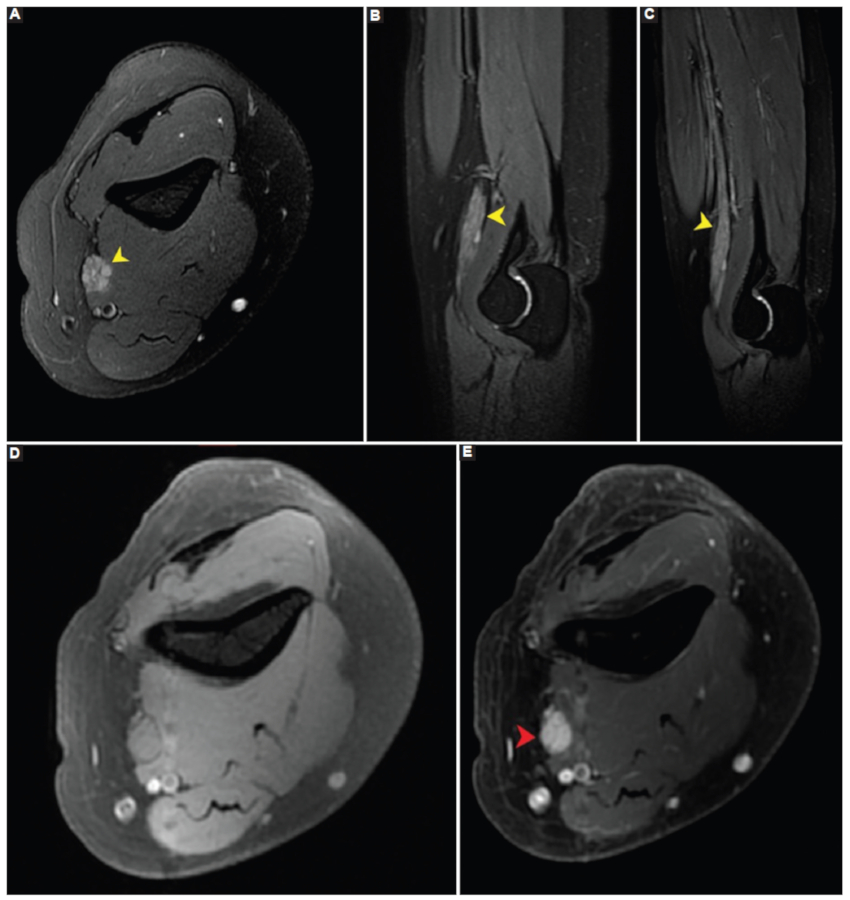

Se realizó neurografía por RM en un equipo 3T (General Electric, Discovery 750, Wisconsin, EE.UU.), con secuencias volumétricas IDEAL (Iterative Decomposition of water and fat with Echo Asymmetry and Least-squares estimation, GE Healthcare, EE.UU.) en pulsos T1 y T2, donde se visualizó un engrosamiento fusiforme del nervio mediano izquierdo, de bordes regulares, con hiperintensidad de señal en las secuencias ponderadas en T2 de varios de sus fascículos (Fig. 1 A-C) e intenso realce luego de la administración de contraste endovenoso (Fig. 1 D y E) (1. Se observaron, asimismo, fenómenos denervatorios en el músculo pronador redondo y flexor digital superficial. Los hallazgos se interpretaron como perineurioma del nervio mediano.

Los hallazgos en RM son el engrosamiento fusiforme del nervio o plexo afectado, en grado variable de sus fascículos, incluso con fascículos preservados, generalmente de considerable longitud. Es característica la preservación del patrón fascicular del nervio («patrón en panal»), con señal isointensa en secuencias ponderadas en T1, hiperintensa en secuencias ponderadas en T2 e intenso realce de los fascículos afectados tras la inyección del contraste endovenoso. Otros hallazgos incluyen el edema por denervación, atrofia y reemplazo graso de los grupos musculares dependientes del nervio afectado2,3,8.